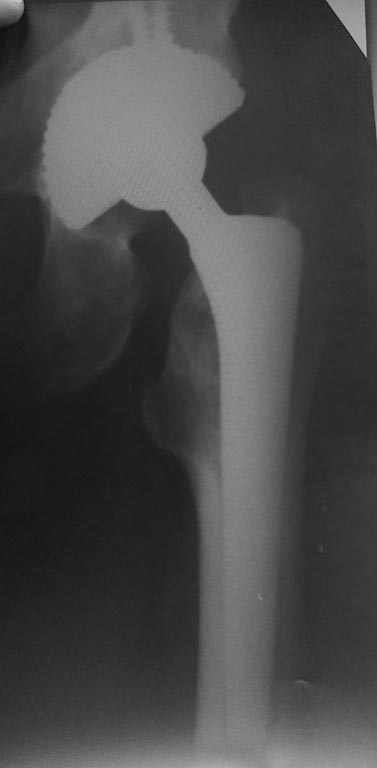

Re: Децентрация головки эндопротеза

Р-грамма 2019 год